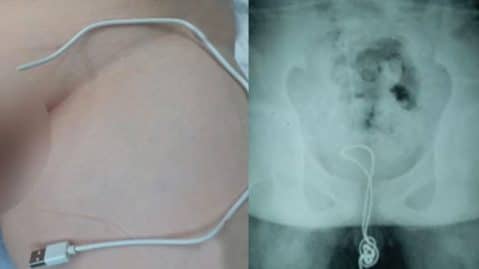

Les téléphones portables avant VS maintenant